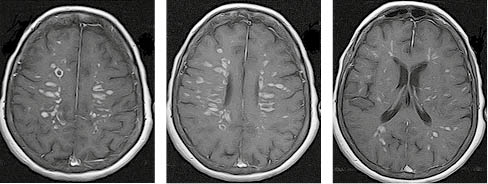

За МРТ-зображення головного мозку пацієнта з ГРЕМ у режимі Т2/Flair та Т1 із внутрішньовенним контрастуванням візуалізуються двобічні вогнища, гіперінтенсивні за Т2/Flair, які в переважно накопичують контраст і розташовані на рівні базальних ядер і таламусів, що є типовою клінічною ознакою ГРЕМ (рис. 2).

/images/nn257-1622023r2_.jpg)